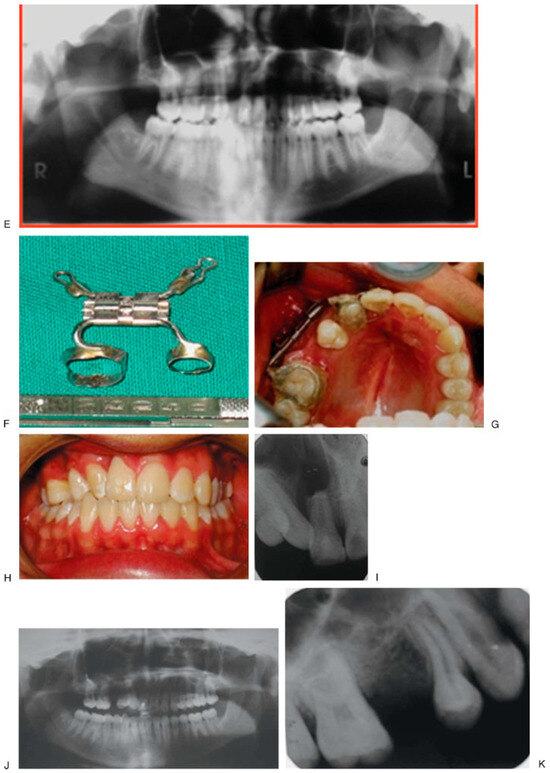

Figure 3. Initial aspect (A–E). Design of the device (F). End bifocal alveolar bone transportation technique (G). Closing of alveolar fistula at 57 weeks of follow-up (H–J). Regenerated new bone behind of the used transport disk (K). - Case 2 was a 16-year-old female patient with sequel of cleft lip and palate and active oronasal fistula, treated with bifocal ABT (Figure 4).

Figure 4. Initial aspect (A–D). There is no anchoring of dental bands, but orthodontic tubes (E). End trifocal alveolar bone transportation technique (F). Aspect at 90 weeks of follow-up (G,H), and radiographics with evidence of closure fissure and osseointegrated implant in the regenerated new bone (I–K). - Case 3 was a 19-year-old male patient with sequel of cleft lip and palate and active oronasal fistula, treated with bifocal ABT (Figure 5).

Figure 5. Initial aspect of the patient; fistula between 9–11 (A–E); alveolar bone transportation technique. Modified Hyrax device (VEGAX) (F–H); at 205 weeks of follow-up (I–K). - Case 4 was a 16-year-old male patient with cleft lip and palate sequel, treated with bifocal ABT (Figure 6).